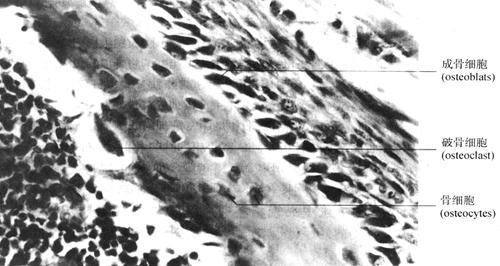

1.骨细胞(osteocyte) 骨骼是一种能够生长发育、造型、重新塑造和修复的活组织,这些都是通过骨的各种细胞的活动来完成的(图2-35)。

图2-35 胎儿指骨(400×)

(1)骨原细胞(osteoprogenitor cells):呈梭形,胞质弱嗜碱性,核椭圆形,淡染,位于骨外膜和骨内膜贴近骨处。是骨组织的干细胞。可分化为成骨细胞。

(2)成骨细胞(osteoprogenitor):有多个突起,胞质嗜碱性,核圆色淡。位于骨组织表面,合成骨基质的有机成分胶原纤维及糖蛋白,这些尚未钙化的基质,称类骨质(osteoid),当钙化后成为骨质。被自身分泌的基质所包围的成骨细胞改称为骨细胞。

(3)骨细胞(osteocyte):是扁平多突的细胞,埋于钙化的骨基质中,其胞体所占的空间称骨陷窝(bone lecuna),突起所在的空间称骨小管(bone canaliculus),内含组织液,以营养骨细胞和输送代谢产物。相邻骨细胞突起间有缝隙连接。

(4)破骨细胞(osteoclast):是多核大细胞,胞质嗜酸性,内含大量的线粒体、溶酶体、吞饮泡。贴近骨基质的一侧有皱褶缘(ruffled border),参与骨的改造及血钙调节。